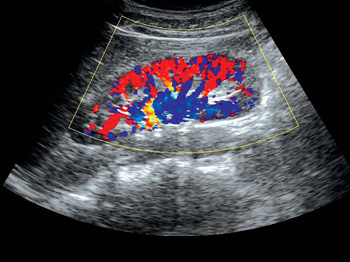

- Цветной доплер CFM

- Функция 3D Color

Цветной доплер. Эта функция поможет в исследованиях сердечно-сосудистой системы. Вы сможете выделить цветом характер кровотока на интересующем вас участке. Кровяной поток, идущий от датчика, отображается синим, к датчику – красным. Турбулентный поток фикс

Функция получения трехмерного изображения в режиме цветового допплеровского картирования. Эта функция поможет вам получить качественные трехмерные цветные изображения при проведении исследования. Нужного эффекта удается достичь за счет использования датчи